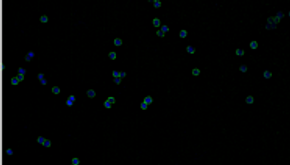

We are delighted that a second Royal Society International Exchanges grant has been awarded to the lab. This time, we will work with Professor Alessandro Podesta, form the Department of Physics, University of Milan, Italy, to investigate the use of advanced microscopy techniques, (AFM and super-resolution) to investigate cancer-associated microbiome markers in breast cancer.